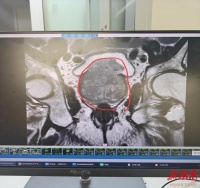

多囊肾是否会发展成尿毒症?概率高吗?

2026年03月27日 20:08